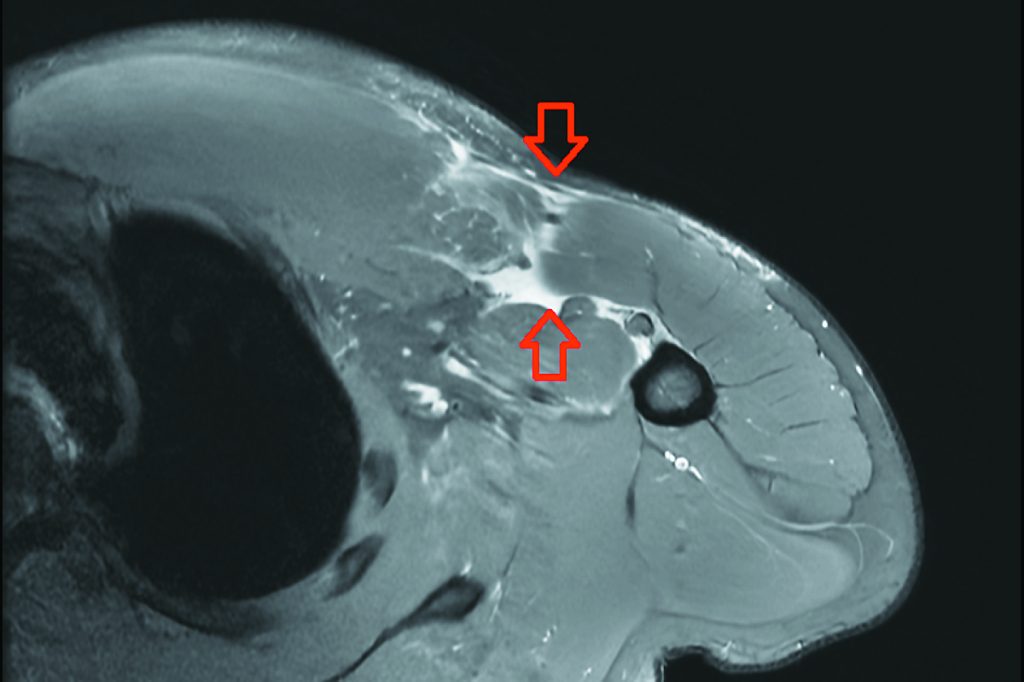

27歲的林先生平時有規律的健身習慣,某次在健身房進行臥推訓練,在休息時放下槓鈴的瞬間,突然感到右側胸口劇烈疼痛,右上肢越發無力,伴隨瘀青腫脹,遂至台北慈濟醫院骨科門診求診。醫師李奕澄藉由理學檢查與核磁共振影像,診斷為右側胸大肌斷裂,隨即安排胸大肌肌腱縫合手術,固定斷裂肌腱。術後林先生按時復健,力量逐步回升,半年後也恢復日常生活。

李奕澄表示,胸大肌斷裂屬於相對罕見的運動傷害,主要發生在20至40歲、長期從事重量訓練的族群,臨床症狀包括急性劇痛、局部腫脹與瘀青、患側力量明顯下降等,外觀上也可能出現兩側胸部不對稱;若未及時治療,斷裂的肌腱可能逐漸回縮並產生沾黏,不僅上肢推舉與支撐力量會受損,外觀變形也可能成為永久性改變,對日常工作、自信心與生活品質造成長遠影響。